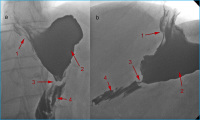

Magenbypass

Abbildung 14: Zustand nach Magenbypass mit Anastomosenleck: a) Zustand nach Anlage eines ersten Stents (1) zur Überdeckung des Lecks, jedoch persistierender, massiver Kontrastmittelaustritt an der gastrojejunalen Anastomose (Pfeilspitze), mit Ausbreitung in den linken Oberbauch; b) überlappende Anlage eines 2. Stents (3) mit nun komplett abgedecktem Leck und unbehinderter Passage. Blindes Ende der Roux-Schlinge (2).

Keywords: GastroenterologieMagenbypassRadiologie